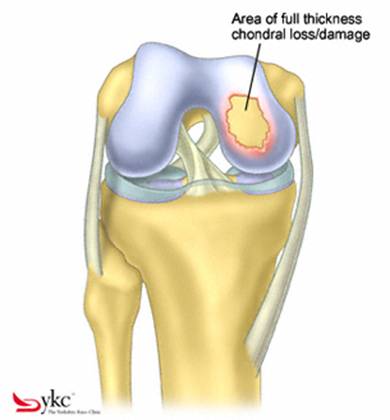

Fig.21. Diagrama unei leziuni cartilaginoase.

Fig.23. Diagrama microfracturi: a. Leziunea; b. Rezultatul interventiei.

Chirurgul trebuie sa fie foarte atent atunci cand examineaza posteriorul condililor femurali. Daca se semnaleaza orice vatamare/rana/deteriorare pe suprafetele articulare, trebuie sa se cerceteze atent calitatea cartilagiului. Orice flapsuri instabile sunt inlaturate prin folosirea unui aparat de ras electric artroscopic sau curette. Apoi, un curette este folosit pentru a debrida stratul de cartilagiu calcifiat de la baza in toata grosimea defectului. Acest pas se bazeaza pe activitatea lui Frisbi, care a demonstrat vindecarea suprafetei articulare superioare la un cal, cand stratul cartilagiului calcifiat este indepartat. Cand indepartam stratul cartilagiului calcifiat, in general nu se foloseste un aparat de ras. Cu un aparat de ras este dificil de controlat cantitatea de os eliminat, si este posibil ca osul subcondral sa fie afectat.

Dupa indepartarea cu succes a stratului de cartilaj calcifiat, o andrea este folosita pentru a face mai multe gauri mici (mirofracturi) in osul expus al defectului condral aflate la distanta de 1-2 mm. Trebuie lasata o punte de oase potrivita intre gauri. Tehnica de microfracturi are numeroase avantaje fata de foraj. Mai intai de toate, creaza o leziune termala mai mica. Mai mult, cu microfracturi, chirurgul este capabil sa intre in zonele dificile ale suprafetei articulare cu un control mai bun asupra adancimii de patrundere. La finalizarea microfracturii, o suprafata aspra este generata pentru a aderenta cheagului de sange care contine celule mezenchimale nediferentiate de la osul subcondral. Trebuie avut grija ca cele mai marginase parti ale leziuni sa fie patrunse de andrea pentru a ajuta la vindecarea tesutului reparator la imprejmuirea suprafetei articulare. Odata ce microfractura este finalizata, pompa artroscopica este oprita pentru a se asigura ca sangerarea maduvei curge din gaurile mici umpland defectul.[54]